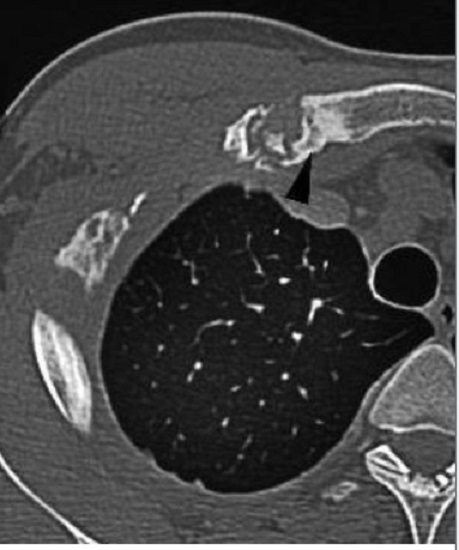

Aspect radiologique TDM du osteite et

hyperostose articulation sternoclaviculaire droit en

coupe axiale d'une syndrome de SAPHO . Image

radiologique TDM en coupe axial |